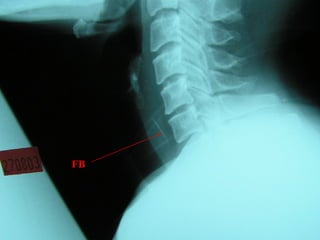

FB Throat - Investigations

Lateral neck XR

CXR

Barium swallow

CT scan – without contrast

Rigid oesophagoscopy

FB